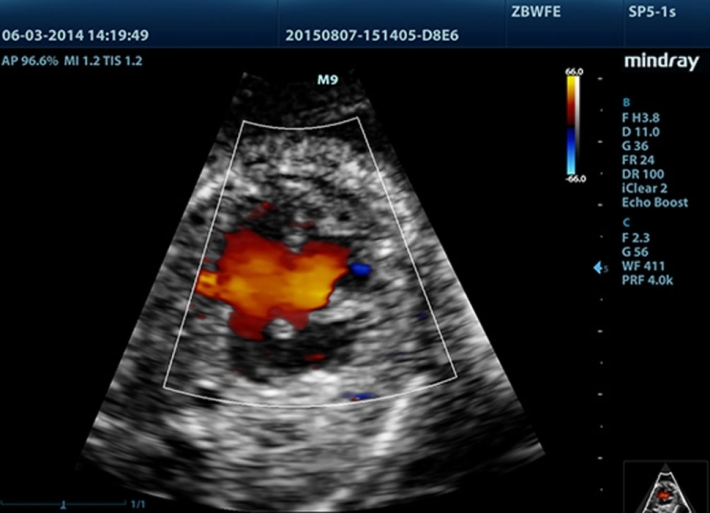

Медицинское оборудование и сервисное обслуживание